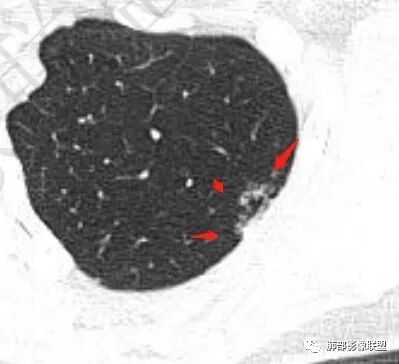

双肺上叶多发结节影及纤维索条影,部分结节内部可见空洞形成,形态欠规则,洞壁厚薄均匀,以胸膜下分布为主,多灶性,多态性,临床年轻女性,体检发现,考虑结核,寄生虫?NTM.

双肺上叶尖段分布为主多发囊腔伴斑点,斑片影,囊腔壁不规则,部分内见分隔。考虑结核可能

两肺多发囊或空洞(部分腔内不干净可见间隔影)+多发结节 (右侧胸膜下的结节显著)+左肺尖斑片影。年轻女性,体检发现。考虑结核?鉴别PLCH(奇异囊加结节,吸烟男性多见),转移瘤(要有原发肿瘤病史)

双肺上叶多发结节影,形态不规则,部分结节内部可见空洞形成,洞壁薄,胸膜下分布为主,年轻女性,体检发现,考虑结核

2.双肺多发薄壁空洞影、条索影及结节影,边界较清楚,密度偏高不柔和,散乱,但有成簇倾向或堆积感,胸膜下分布为主,双肺上叶分布为主。

3.空洞相当不规则,缺乏张力,未见血管穿行,未见壁结节,未见液平。